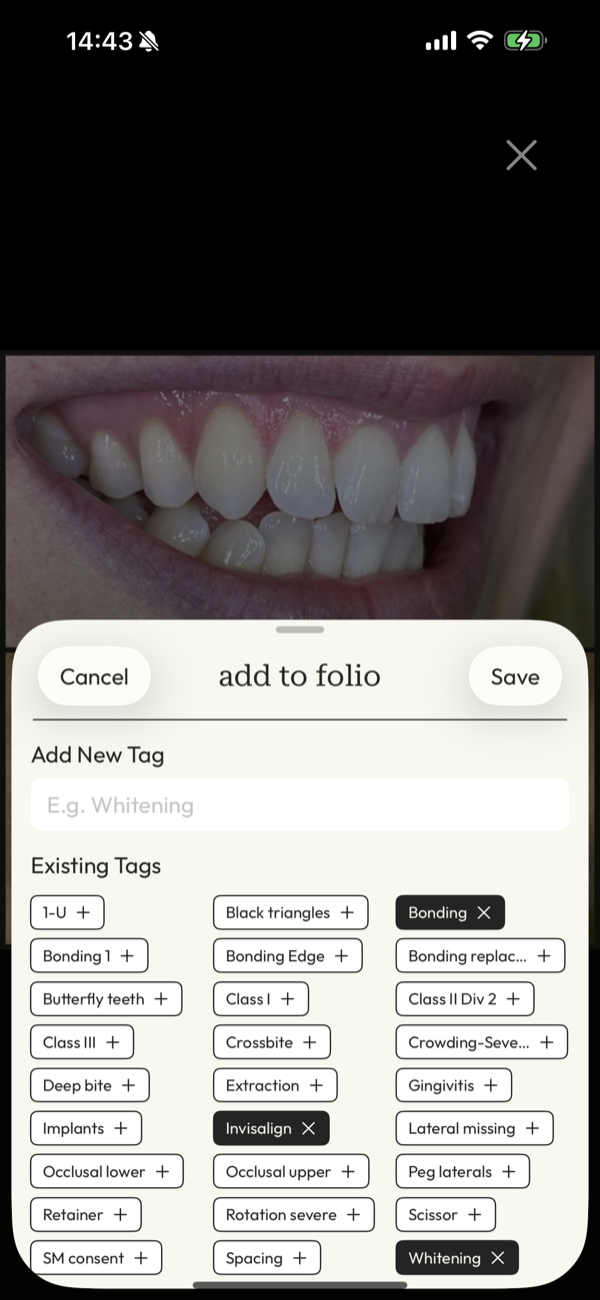

find the right photo in an instant

Give clients confidence and clarity in the moment with intuitive tagging that makes images just a tap away whenever you need them.

DentalFolio is designed around how clinical photography is actually used: by patient, by case, and for clear before-and-after presentation, with consent information kept alongside the images.

The real time sink is finding the right images when they're needed, often just before or during a patient conversation. DentalFolio keeps photos organised by patient and case, removing the need to scroll through unrelated images.